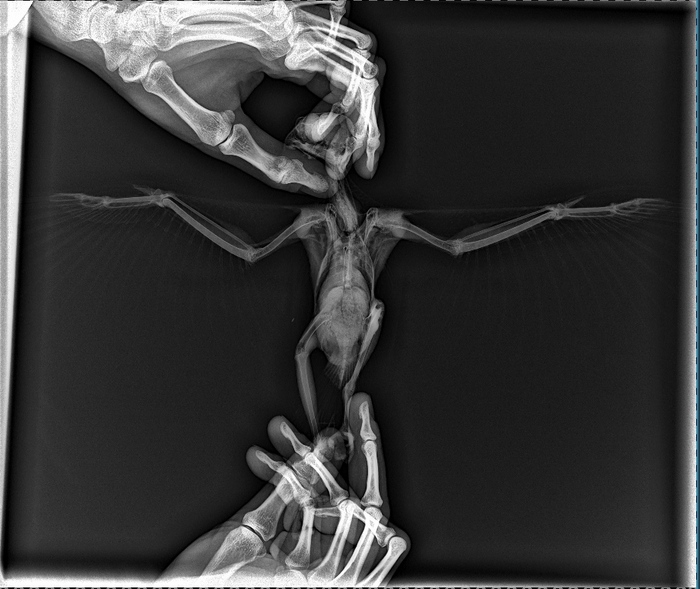

Утром следующего дня я дозвонился до Центра реабилитации диких птиц "Воронье Гнездо". Сказали что птицу примут, но нужно сделать рентген. Квест предстоял ещё тот. Сам я живу в г. Щёлково. В городе есть клиника с рентгеном, но делать для хищной птицы там забоялись, пришлось мчать в г. Балашиха, где в ветеринарной клинике на Трубецкой 69 приняли нас без проблем. Вдвоём с сотрудницей клиники мы уложили птицу не стол, я держал за лапы и голову, она растянула крылья, а второй сотрудник произвёл рентгенографию.

Видели когда-нибудь рентгеновский снимок сокола? Теперь видели.

На снимке ничего скабрезного не обнаружилось, возможно имеет место повреждение плечевого сустава или ушиб.